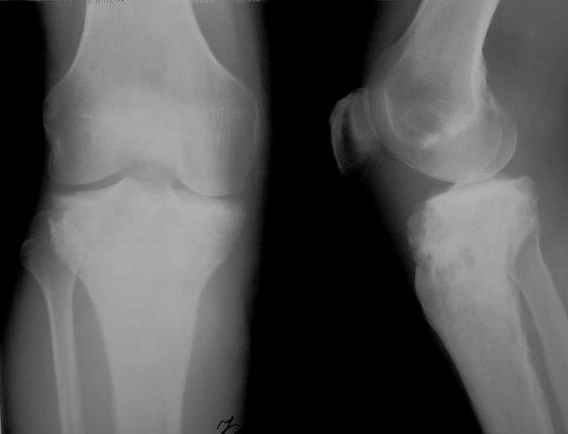

Всем привет!Кому интересно - может лицезреть мое личное наблюдение первичной костной лимфомы с поражением правой большеберцовой кости (см. аттач). Пациент: мужчина, 46 лет. Анамнез прослеживается в течение 1,5 лет - начало заболевания с появления болей.С уважением, Виталий Тазалов.

Ещё одно клиническое наблюдение - лимфома кости, до и после ПХТ и лучевой терапии.